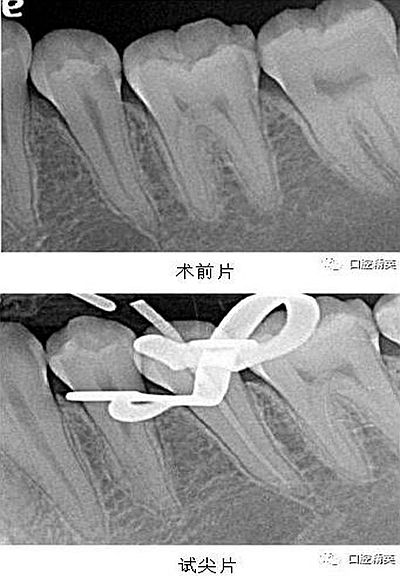

X-ray 可見:35 遠中齲壞累及髓腔,牙周膜增寬。

處置:經(jīng)患者及家屬知情同意后,35 局麻,放置橡皮障,去腐,開髓,可見黑色感染物流出,定位根管口,建立直線通路,10# K 銼疏通根管,確定工作長度(19mm),機用鎳鈦器械(M3),次氯酸鈉全程浸泡沖洗,預備根管至 35 號,0.04 錐度,2ml EDTA 沖洗液緩慢勻速沖洗,超聲蕩洗。試主尖 X-ray 可見恰充,吸潮紙尖拭干根管,導AH-Plus 糊劑,連續(xù)波熱牙膠垂直加壓充填,術(shù)后 X-ray可見根管恰充,SDR 封閉根管口,復合樹脂充填窩洞,恢復牙齒形態(tài),調(diào)牙合,拋光。醫(yī)囑